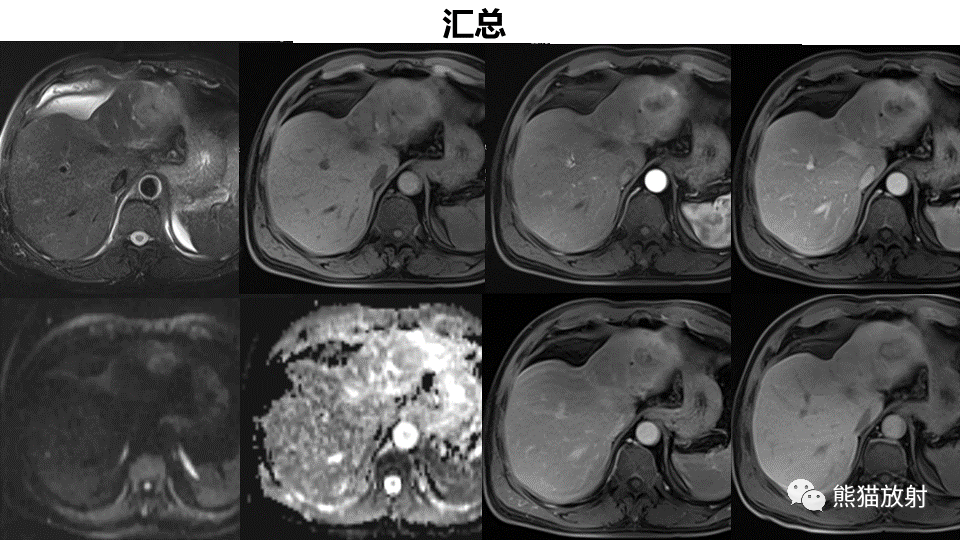

【PPT】肝内胆管细胞癌 VS 肝脓肿